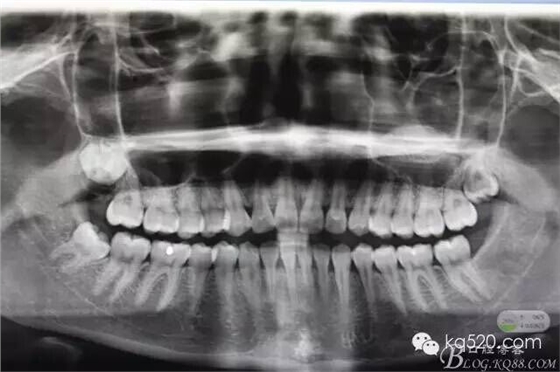

閆xx、女、19歲,主訴:右側下頜后牙不牙齦適數(shù)日。??茩z查:48未萌出、47遠中有深的盲袋、可探及牙冠。牙齦輕度紅腫,x光:48近中傾斜、雙根。診斷:近中埋伏阻生。建議拔除,患者同意治療方案,簽手術知情同意書。術前設計:考慮患者比較年輕,近中傾斜不大。計劃設計微切口、不分牙、微創(chuàng)拔除。

圖1.術前的x光影像檢查,48近中輕度傾斜。